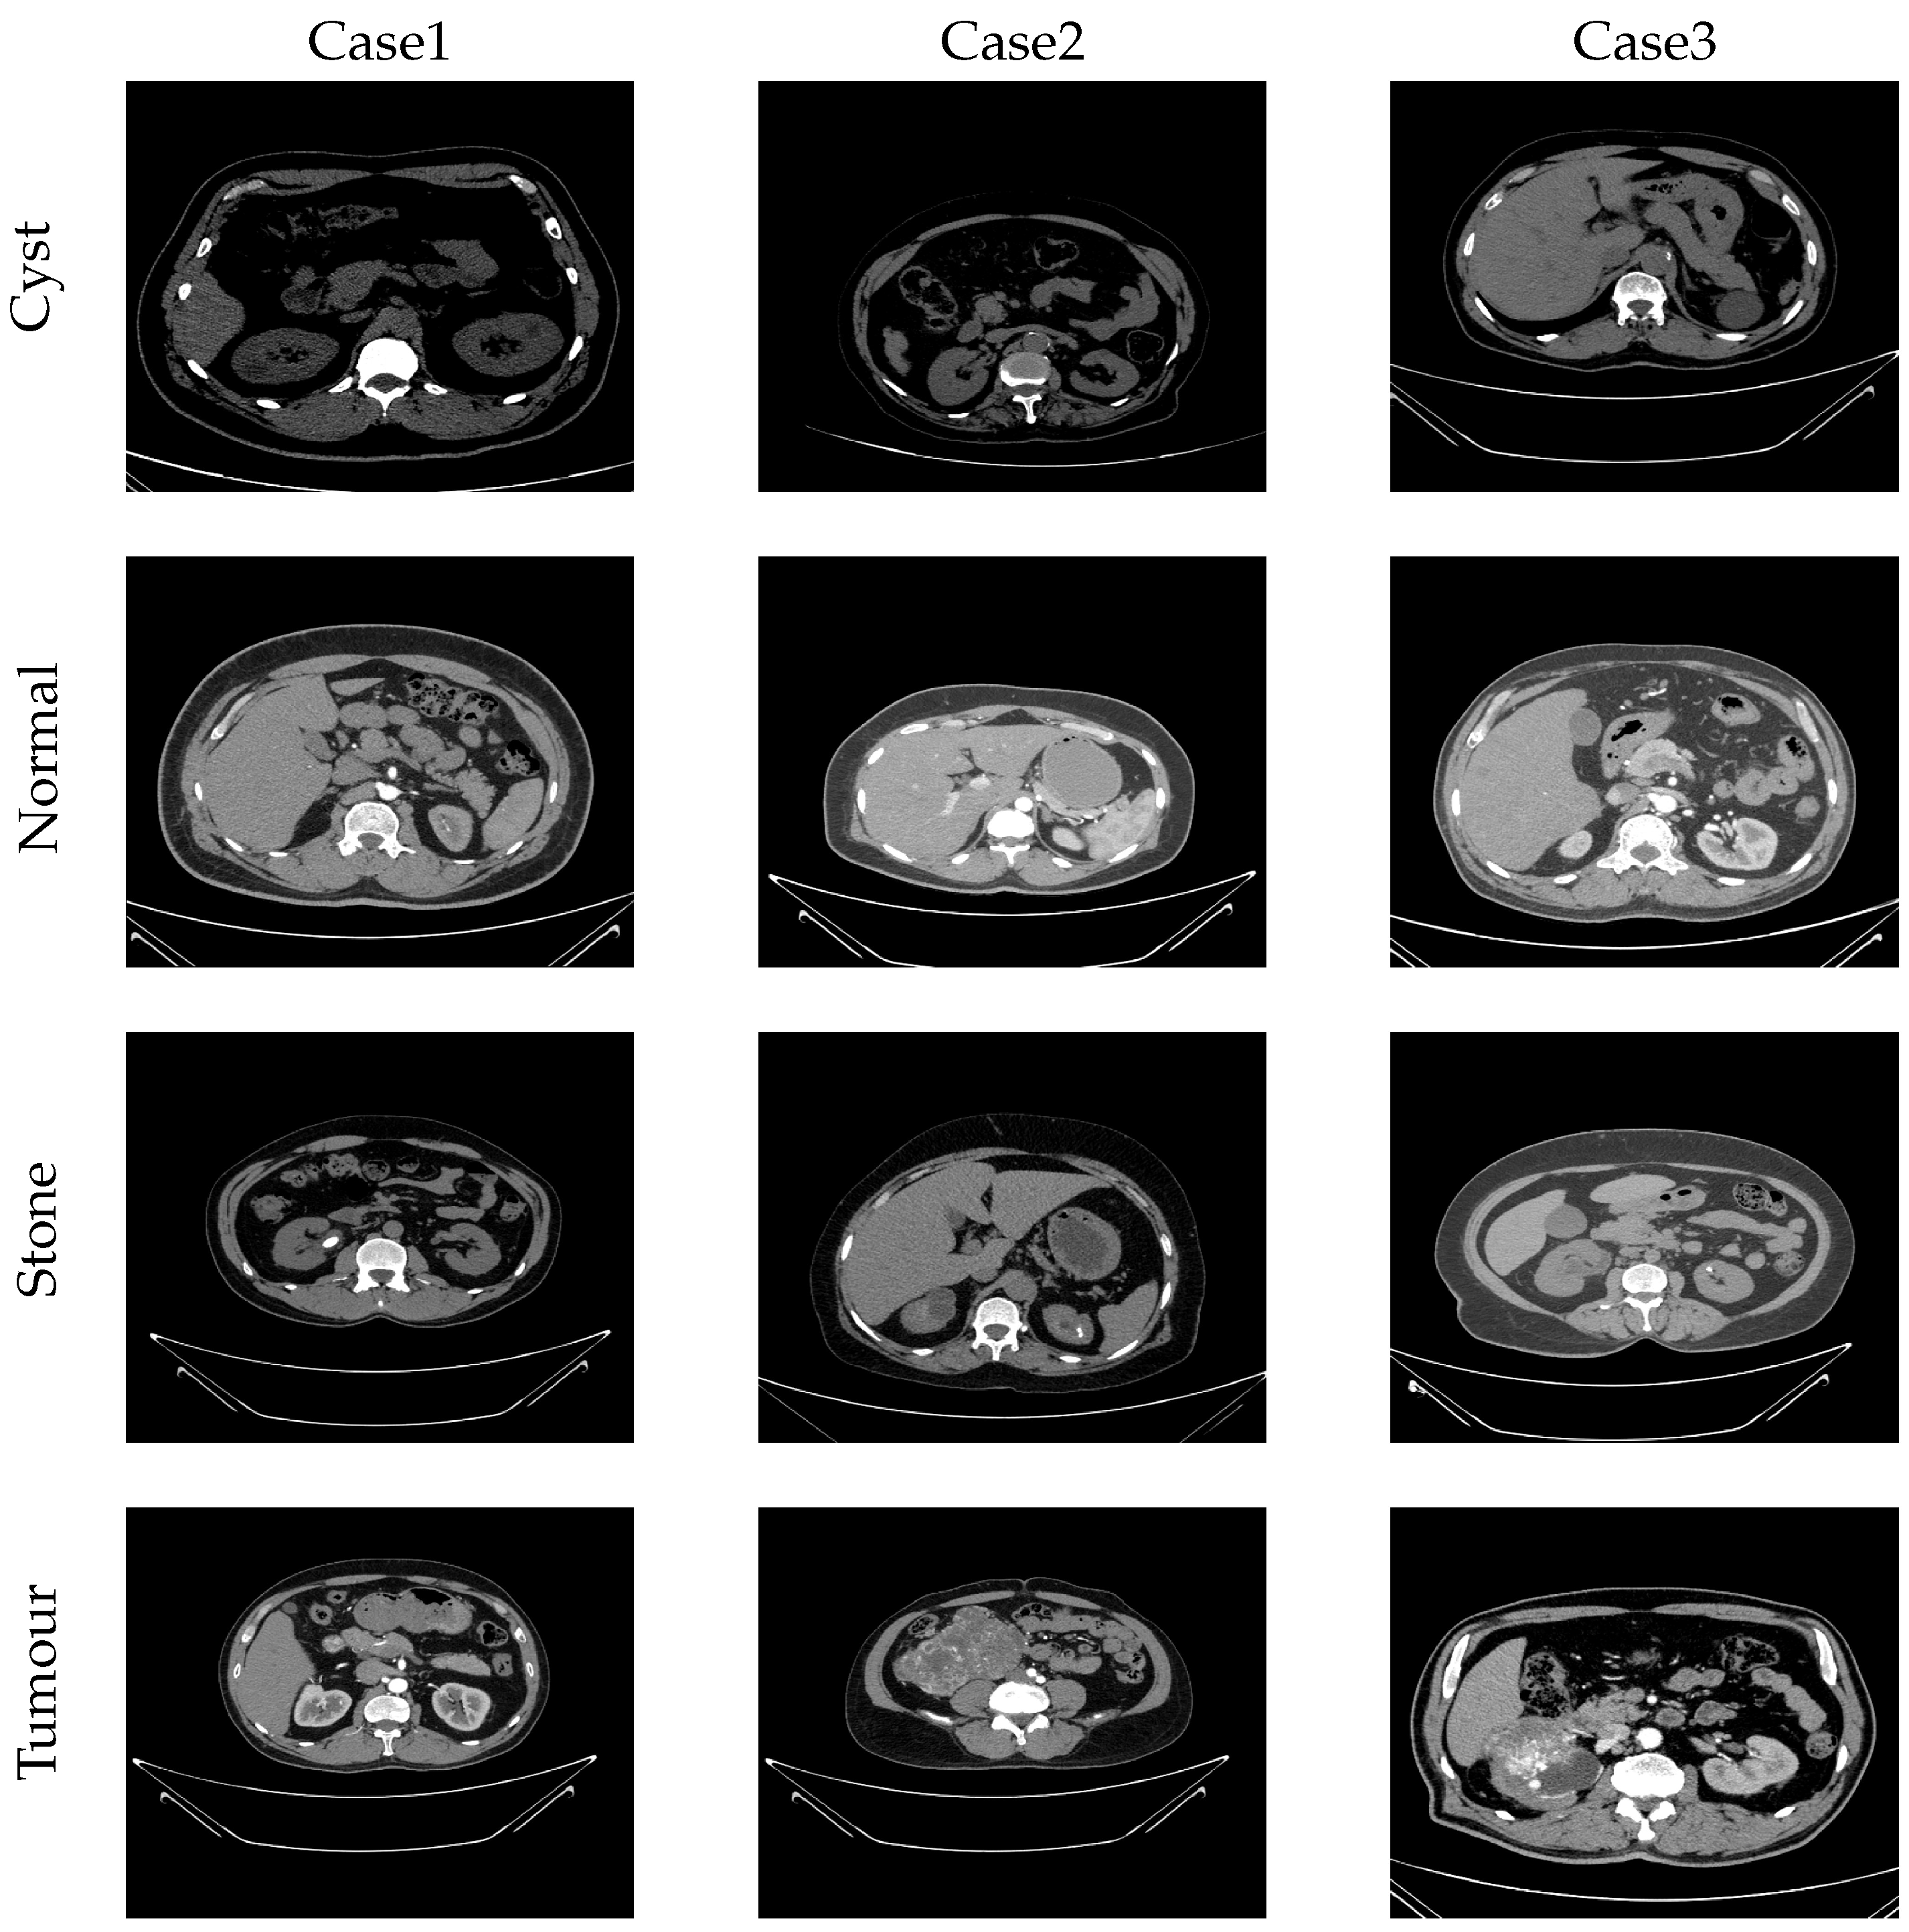

4.2. Used Dataset